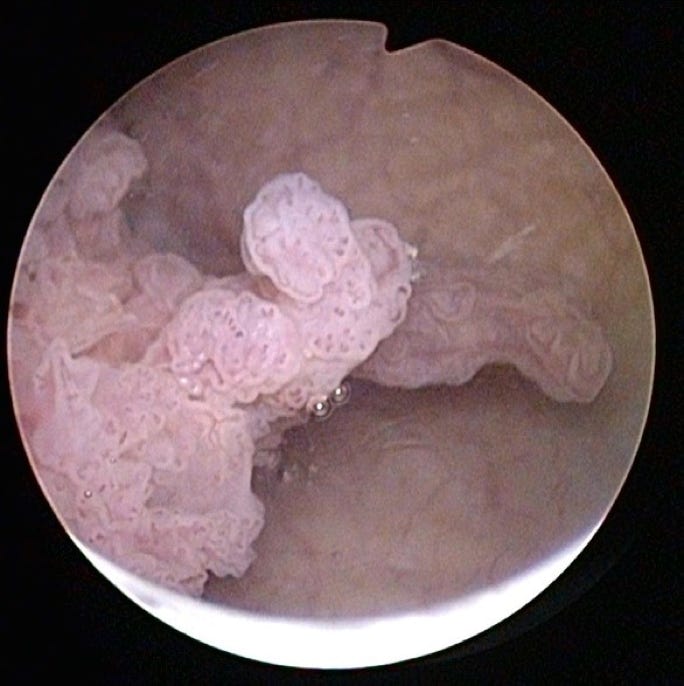

- Endoskopie (flexible Zystoskopie)